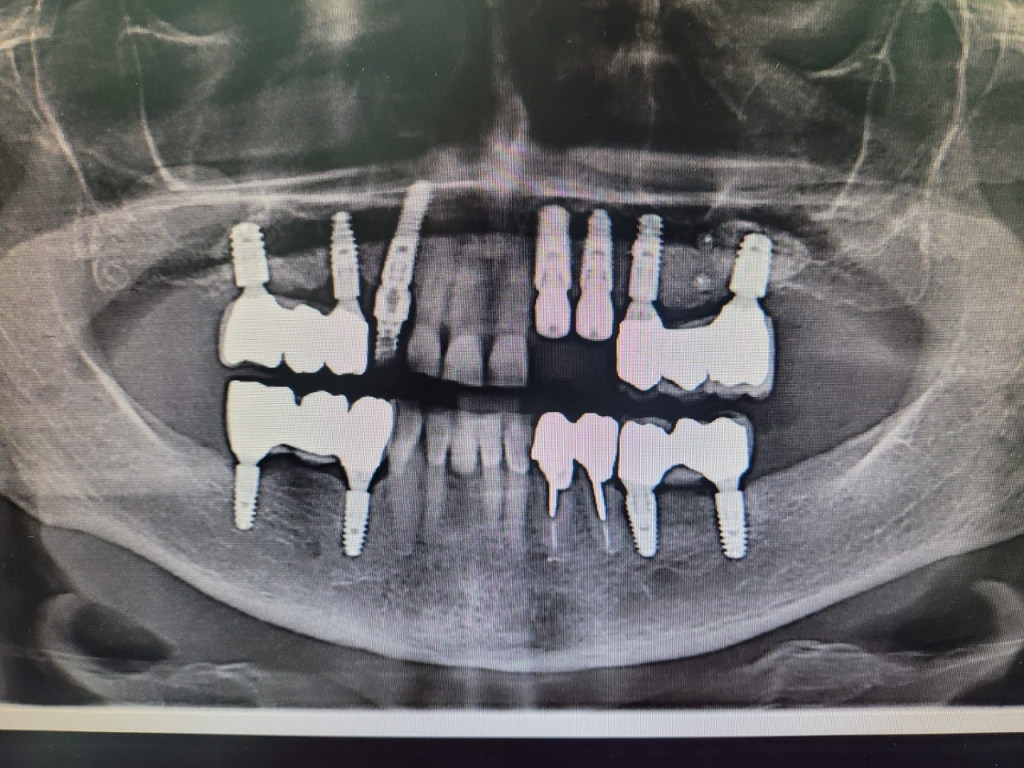

Пациентке 69 лет.

План: удаление имплантата 22 с одномоментной установкой имплантатов 22, 23 (зуб 23 уже удален к моменту операции). Плюс немедленная нагрузка временными коронками.

Установлены имплантаты с укороченным протоколом сверления (2.0 на всю глубину, фреза 3.3 на 7 мм):

Импро Респект 4.5х12, торк более 40 Н/см.